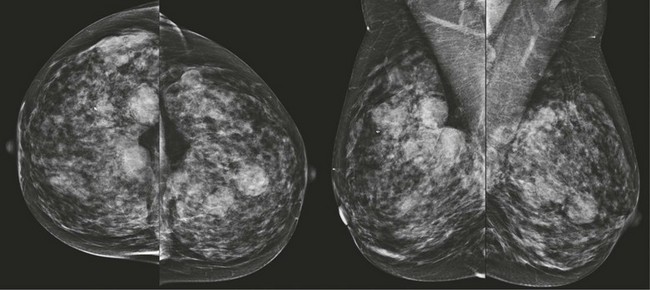

FIGURE 8-1 Multiple Bilateral Benign Masses.

Screening mammogram on a 48-year-old woman showing multiple bilateral similar-appearing masses with partially circumscribed margins. This woman had bilateral cysts previously demonstrated by US. There were no suspicious changes compared with previous mammograms. The patient was assigned BI-RADS 2, and no suspicious changes have occurred in over 2 years on subsequent mammography.